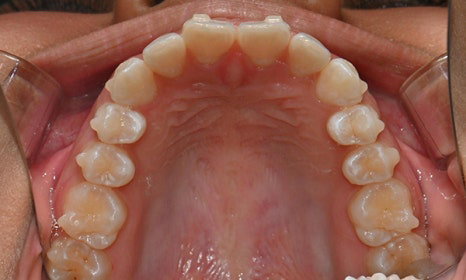

치아 상태는 어땠냐면요:

위아래 앞니 사이에 공간이 벌어져 있었어요.

앞니가 삐뚤빼뚤한 덧니도 있었죠.

윗니와 아랫니가 너무 깊게 맞물리는

과개교합이 있었어요.

왼쪽 아래 작은어금니가 90도 돌아가 있었는데,

이로 인해 왼쪽 치아 배열과 교합이 좋지 않았죠.

초진시 구내사진 (2025. 3.31)